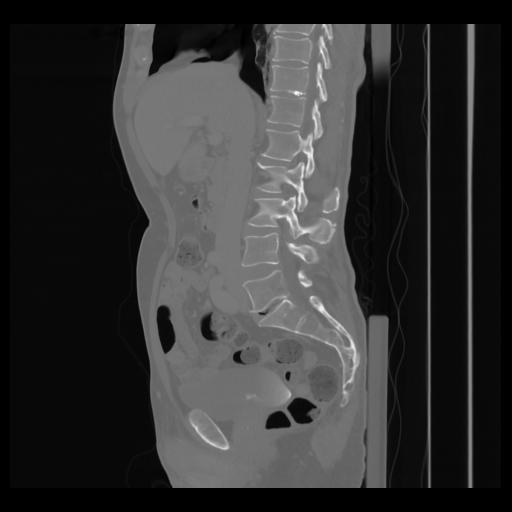

36 CUERPO,CE,Sagittal,3.000,CUERPO,Sagittal,